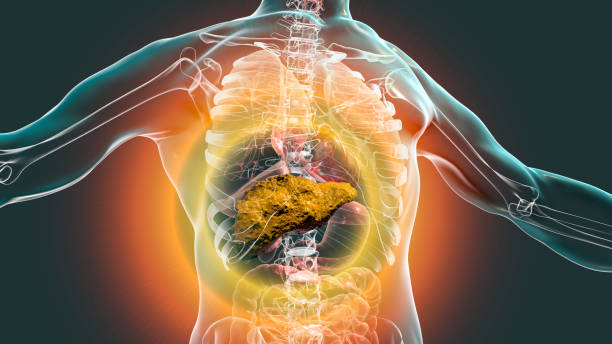

복부 부기 또는 물질감

간이 비대하게 부어오르거나, 간 주변 조직에 암이 생겨 부풀어오르는 현상으로 인해 발생할 수 있습니다. 이러한 증상은 복부의 불편감, 가슴부분의 압박감, 숨이 차는 느낌 등을 유발할 수 있습니다. 또한, 복부가 부풀어오르거나 물질감이 느껴지면서 식사량이 줄어들 수 있으므로 체중 감소에도 영향을 미칠 수 있습니다.

가슴 또는 우측 상복부의 불편감

간은 몸의 오른쪽 상단에 위치하며, 간암이 발생하면 간이 커지거나 암 조직이 생길 경우 가슴이나 우측 상복부에 불편감을 느낄 수 있습니다. 이러한 불편감은 종종 차가운 느낌과 함께 발생하며, 느슨한 옷을 입거나 몸을 움직일 때 더욱 두드러질 수 있습니다.